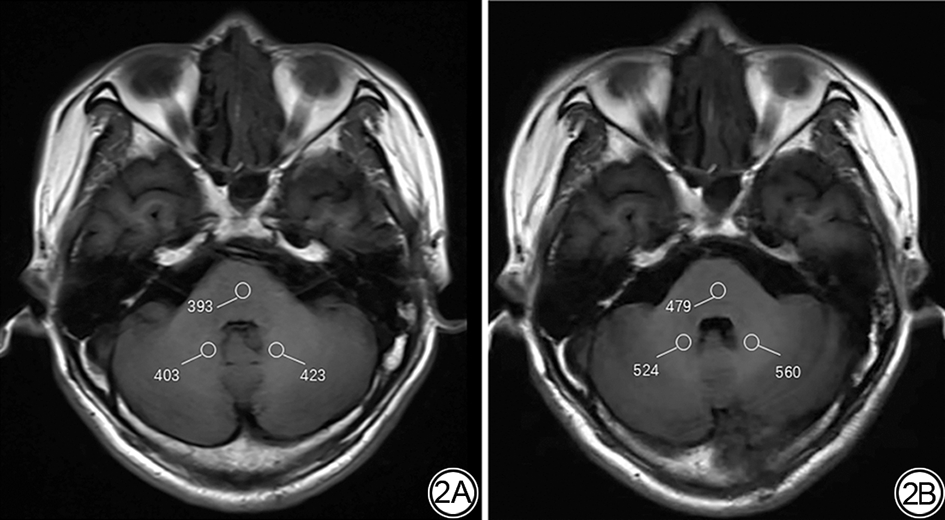

不同患者多次MRI增强检查后平扫T1WI DN/脑桥SI比值高于首次增强前DN/脑桥SI比值(图1图2),呈非线性关系。

图2  男,44岁,脑胶质瘤,标准感兴趣区分别选择于左右侧DN、脑桥。2A:首次MRI平扫T1WI,DN未见明显异常信号,DN/脑桥的SI比值为1.05。2B:第8次MRI增强后,头颅T1WI平扫DN信号增高,DN/脑桥的SI比值1.13。SI:信号强度;DN:小脑齿状核。

Fig. 2  A 44-year-old male with glioma. Standard regions of interest are selected in the bilateral dentate nuclei and the pons. 2A: Initial non-contrast T1-weighted MRI shows no significant abnormal signal in the cerebellar dentate nuclei, and SI ratio of DN-to-pons is 1.05. 2B: Following the 8th MRI contrast administration, an increased signal intensity is seen in the dentate nucleuson non-contrast T1-weighted imaging, and SI ratio of DN-to-pons is 1.13. SI: signal intensity; DN: dentate nucleus.